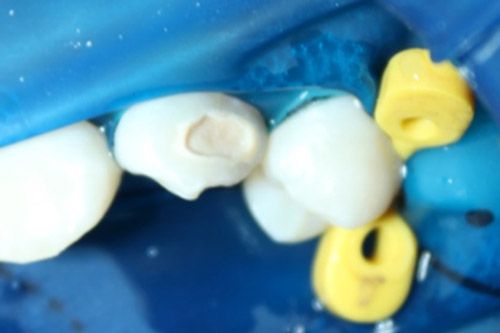

En la cavidad se colocó una resina compuesta, se le pulió con discos de lija superfix y se le dio brillo con un disco de fieltro impregnado con pasta Polimax de TDV.

Resultado final

La resina infiltrante Icon, se puede utilizar como complemento a tratamientos más invasivos, en casos donde se cuenta con lesiones blancas de poca profundidad.